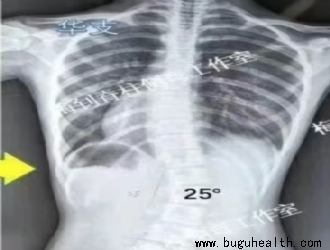

青少年脊柱侧弯